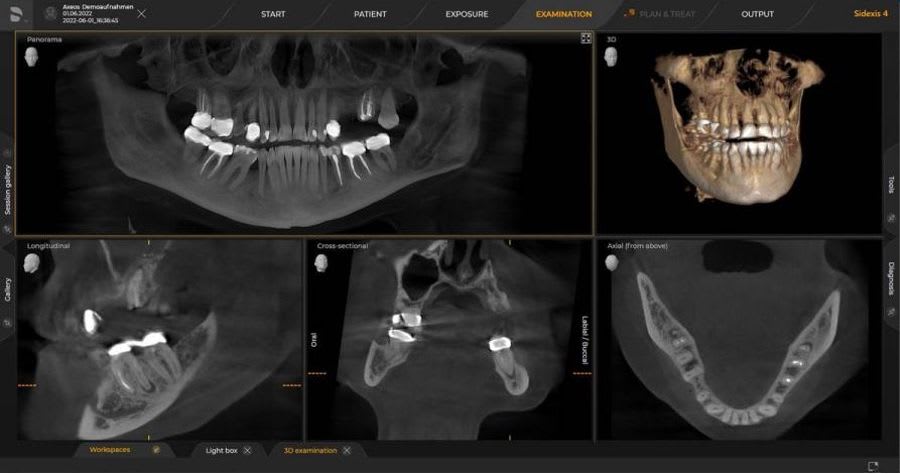

Cone Beam Computed Tomography (CBCT) har etablert seg som en sentral bildediagnostisk metode innen odontologi, implantologi og kjevekirurgi. Teknologien gir tredimensjonale bilder med høy oppløsning og lavere stråledose enn konvensjonell CT. Tradisjonelt har enkelte CBCT-enheter inkludert en SCOUT-funksjon – en forhåndsvisning som hjelper med posisjonering før endelig skanning. Spørsmålet er: Er SCOUT-funksjonen nødvendig i moderne CBCT-systemer? Nyere forskning og teknologiske fremskritt indikerer at svaret ofte er nei.

Nyere forskning viser at SCOUT-funksjonen har begrenset nytte i dagens CBCT-teknologi. En studie publisert i Dentomaxillofacial Radiology (2024) konkluderte med at SCOUT-bilder gir minimal diagnostisk verdi og lav reproduksjon av funn sammenlignet med CBCT-volumet [1]. En dosimetrisk analyse i Clinical Oral Investigations (2024) viste at SCOUT gir en ekstra stråledose på 0,7–6,9 µSv, som er liten, men unødvendig dersom moderne systemer sikrer korrekt FOV uten SCOUT [2]. Dette er i tråd med ALARA-prinsippet. I tillegg har nyere CBCT-enheter som Dentsply Sirona Axeos avanserte posisjoneringshjelpemidler, inkludert laserindikatorer, hodeholdere og automatisk FOV-tilpasning, som gjør SCOUT overflødig i de fleste kliniske situasjoner.

SCOUT-funksjonen har historisk hatt en rolle i CBCT-teknologi, men dagens avanserte posisjoneringssystemer og programvare gjør den i stor grad overflødig. Å velge en CBCT uten SCOUT gir fordeler som lavere stråledose, raskere og enklere arbeidsflyt, kostnadseffektivitet og bedre pasientopplevelse. Dette er i tråd med gjeldende retningslinjer for strålevern og optimalisering av diagnostiske prosedyrer.